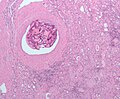

Features:

• Material with out nuclei.

• May be honeycomb-like, cartilage-like or muscle-like.

• May have a glassy appearance - see oxidized cellulose‎.

• Often homogenous or patterned.